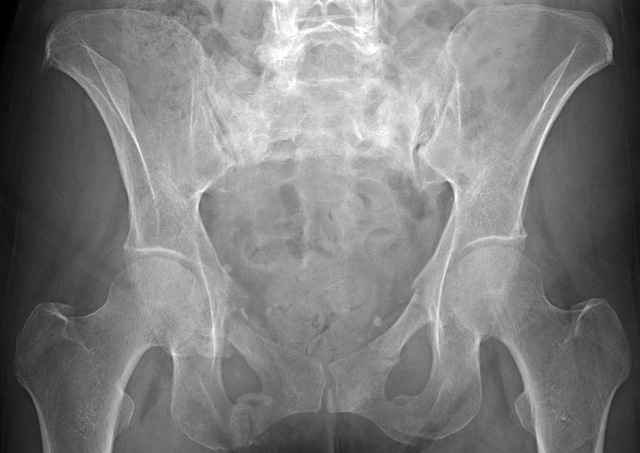

3 Months After Fall

Continued Pain & Immobility

(+) Instability to Compressive Manual Exam